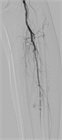

1. LEADは急性下肢虚血と慢性下肢虚血に大別される改訂JG)。

1. 慢性下肢虚血は無症候性と症候性に分けられ、症候性は間歇性跛行と包括的高度慢性下肢虚血(CLTI)に分けられるJG)。